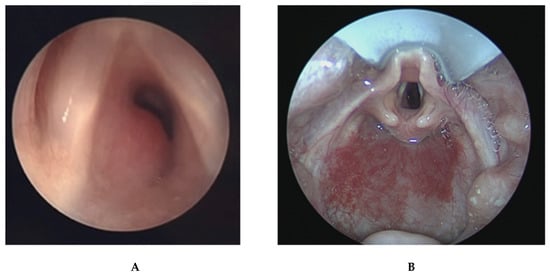

2.12.2. Choanal Atresia